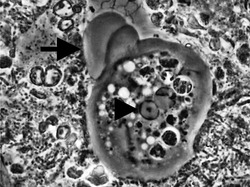

| Entamoeba gingivalis from periodontal pocket [1] | |

It is found in the mouth[5] inside the gingival pocket biofilm near the base of the teeth, and in periodontal pockets.[1] Entamoeba gingivalis is found in 95% of people with gum disease and rarely in people with healthy gums.[6][7] Cyst formation is not present; therefore transmission is direct from one person to another by kissing, or by sharing eating utensils. Only the trophozoites are formed and the size is usually 20 micrometers to 150 micrometers in diameter. Entamoeba gingivalis have pseudopodia that allow them to move quickly and phagocytise the nucleus of polynuclear neutrophils by exonucleophagy in periodontal disease.[8] Their spheroid nucleus is 2 micrometers to 4 micrometers in diameter and contains a small central endosome. There are numerous food vacuoles, which consists mostly of phagocytosed PMN nucleus, blood cells, and bacteria. It also causes pyorrhoea.

The main activity of the amoeba Entamoeba gingivalis in the infected periodontal crevices, besides moving, consists in feeding on the nucleus of white blood cells. The amoeba penetrates into the cytoplasm to reach the nucleus and literally suctions its contents via the negative pressure of the pseudopod. The food so gulped down is gradually digested inside the endoplasm. Phagocytosis can sometimes continue for more than 20 polynuclear neutrophil nuclei. This activity leaves a denucleated cell, unable to achieve either its NETS activity or its preprogrammed apoptosis. It will release PMN-uncontrolled proteolytic enzymes on surrounding tissues and could be considered a pathogen from this vampirising activity.